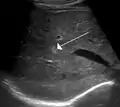

Hemangioma of the liver as seen on ultrasound